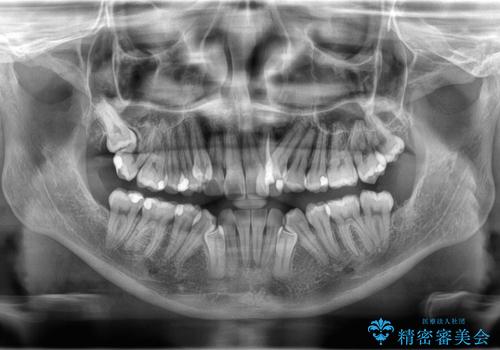

- 「歯のでこぼこを治したい」を主訴に来院された患者様です。 上下ともに、歯のでこぼこが強く、上下左右4の抜歯をし、ワイヤー矯正で治療を行いました。

かなり綺麗に並ぶ事ができ大変満足していただけました。

叢生量がかなり多かったのですが、歯肉退縮も失活歯も無くとても綺麗な歯並びになりました。